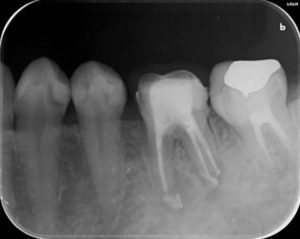

歯の根の治療中のレントゲン写真です。

歯の根の中を清掃する器具を入れています。根の中のばい菌を除去してきれいにしています。